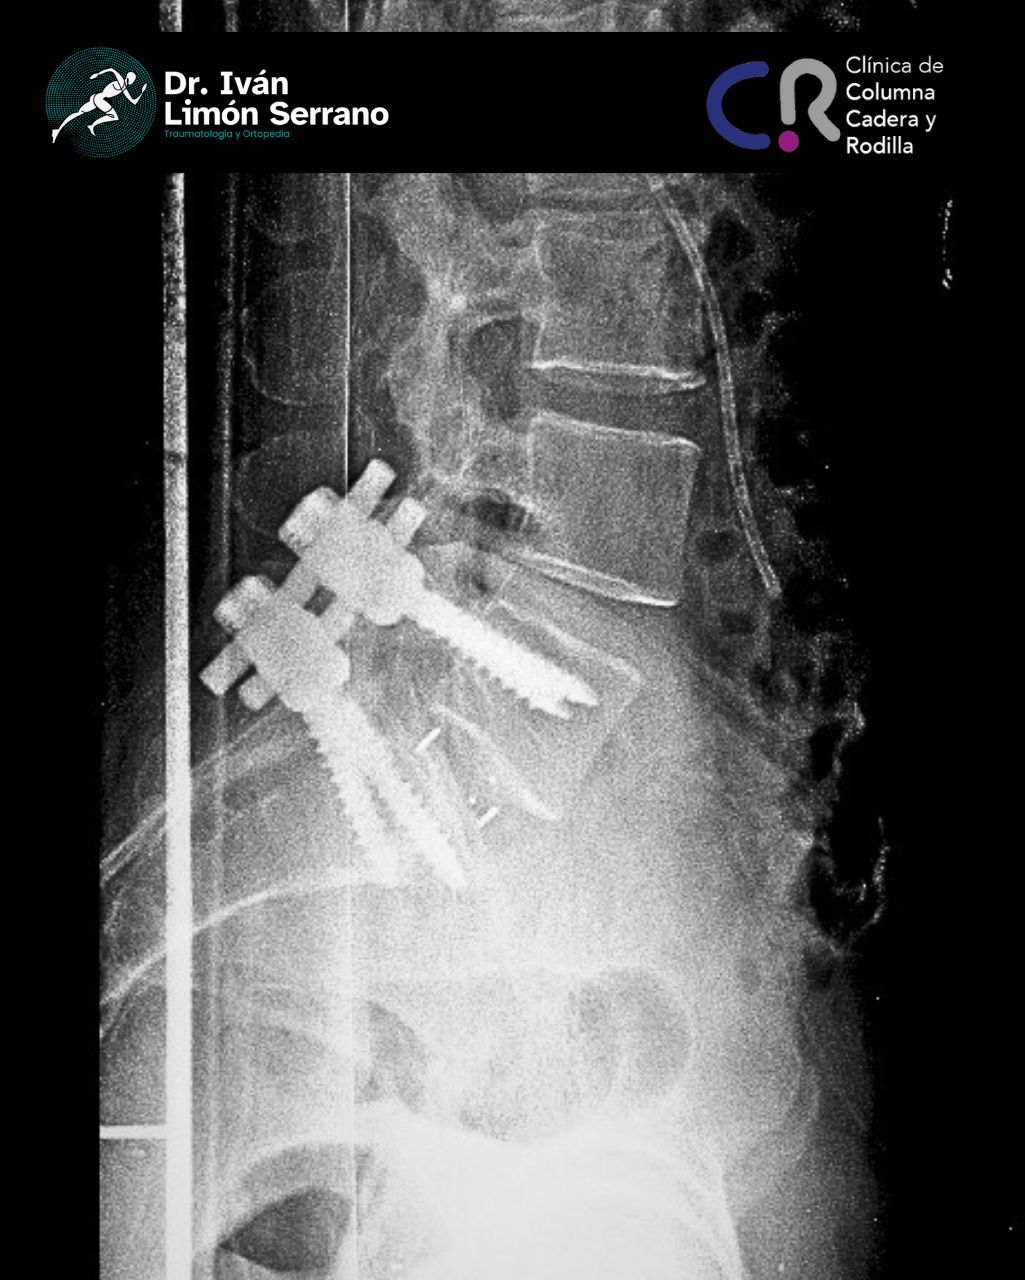

• Cirugía de columna

• Cirugía columna

Hernia de disco

Es una lesión que afecta a las estructuras de la columna vertebral, específicamente discos intervertebrales los cuales son estructuras blandas de consistencia gelatinosa cuya función es actuar como un amortiguador que absorbe el impacto y permite el movimiento de las vértebras. En ocasiones como ocurre durante los esfuerzos y los movimientos bruscos el disco se somete a una gran presión con lo que su anillo fibroso se desgarra, bien sea parcial o totalmente; este desgarro origina un trayecto por donde el material gelatinoso sale de su sitio originándose una hernia discal.